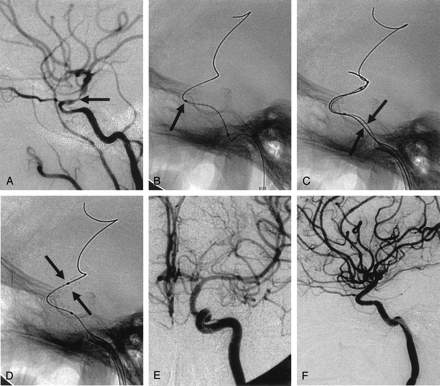

Waiting method. A, Anteroposterior left ICA angiogram shows >60% stenosis (arrow) of the M1 portion of the MCA.

B and C, Standard technique for stent navigation failed (not shown). Anteroposterior views obtained after the stent-delivery system was withdrawn show the angled microwire in the cavernous ICA (arrows).

D, After 20 minutes of waiting, anteroposterior view shows that the angle of microwire changed (black arrow), and navigation of the delivery system (white arrow) into the target lesion is successful.

E, Balloon-mounted coronary stent is successfully deployed (arrow).

F, Anteroposterior left ICA angiogram after stent placement reveals sufficient and smooth dilatation of the stenotic segment (arrow).